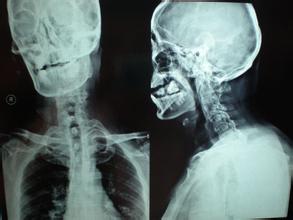

1、起病缓慢,强直性脊柱炎早期症状不明显,定位也不清楚。常感腰背痛,渐感腰部活动不灵活,晨起明显,活动后好转,久坐后活动又不灵活,症状日渐加重,并向上发展。

2、腰痛:腰痛或不适是强直性脊柱炎最常见的病状,发生率90%左右。其发生隐匿,常为隐痛,难以定位。开始时病人常觉得疼痛或不适,部位在臀深部,疼痛严重者常位于骶髂关节,有时可放射至髂嵴或大腿后侧。疼痛可因咳嗽、喷嚏或其他牵扯腰背的动作而加重。开始腰背疼痛可为单侧或间歇性,以后逐渐进展为双侧、呈持续性伴僵硬感。部分病人一开始就出现腰痛,腰痛严重时病人下床都非常困难,此是本病与腰痛病的鉴别要点之一。

3、关节疼痛:最先出现在骶骼关节,可先在一侧,继之对侧发生,也可同时双侧发病。骶髂关节处有压痛,骶髂关节试验阳性。